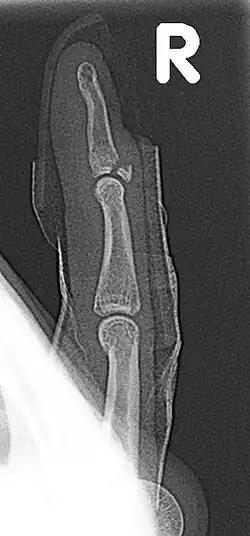

Fracture of the dorsal base of the distal falange by extensor tendon avulsion (Busch fracture)

In medicine a Busch fracture[1] is a type of fracture of the base of the distal phalanx of the fingers, produced by the removal of the bone insertion (avulsion) of the extensor tendon. Without the appropriate treatment, the finger becomes a hammer finger. It would correspond to the group B of the Albertoni classification.[2] It is very common in motorcycle riders and soccer joggers, caused by hyperflexion when the tendon is exercising its maximum tension (the closed hand tightening the clutch lever or the brake lever).[3][4]